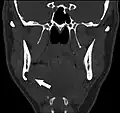

Stafne bone cavity seen on coronal CT -

Stafne bone cavity seen on axial CT